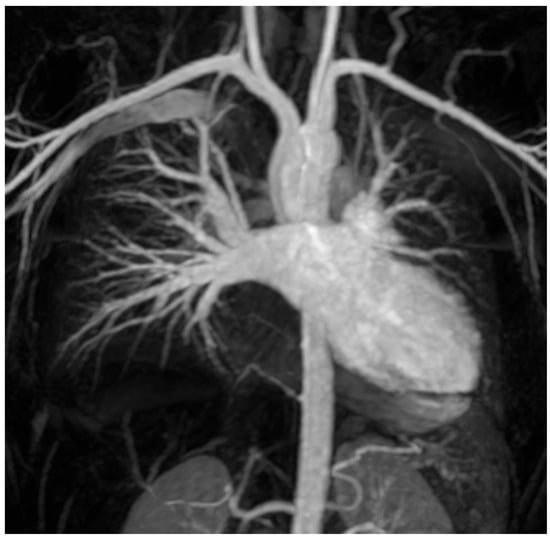

Pulmonary Vein Mapping